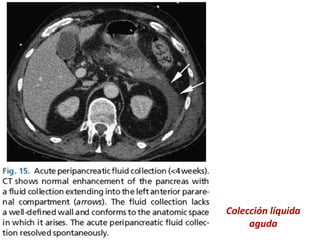

PERIPANCREATICO AGUDO (APFC):

•Fluido peripancreático que surgen en los

pacientes con el IEP durante las primeras 4

semanas.

•Causados por inflamación pancreática y

peripancreática o por rotura de una o más

pequeñas ramas del conducto pancreático.

•Se ubican en el retroperitoneo, son generalmente

perilesionales y no tienen pared perceptible.

Colección líquida

aguda